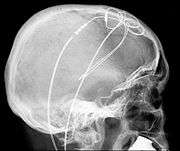

Mrs Geraets-Smits claimed the refusal of reimbursement for treatment for Parkinson’s disease in Kassel, which she believed was better than that available in the Netherlands by focusing on individual symptoms, was contrary to TFEU article 56. Mr Peerbooms received neurostimulation treatement in Innsbruck, which likewise would not have been covered in the Netherlands. Experts testified in both cases that it was unjustified or experimental. Dutch social insurance covered medical costs of low income people, but only if it was approved. Funding came from individual premiums, from the state, and some from other private insurance funds. Geraets-Smits and Peerbooms had paid up front in Germany and Austria. Dutch law said authorisation had required that (1) treatment had to be regarded as ‘normal in the professional circles concerned’, and (2) ‘necessary’ so that adequate care could not be provided without undue delay by a care provider in the home state. The prior authorisation requirement was challenged as being contrary to TFEU article 56. Governments submitted that hospital services were not an economic activity if it was provided free of charge under a sickness insurance scheme.